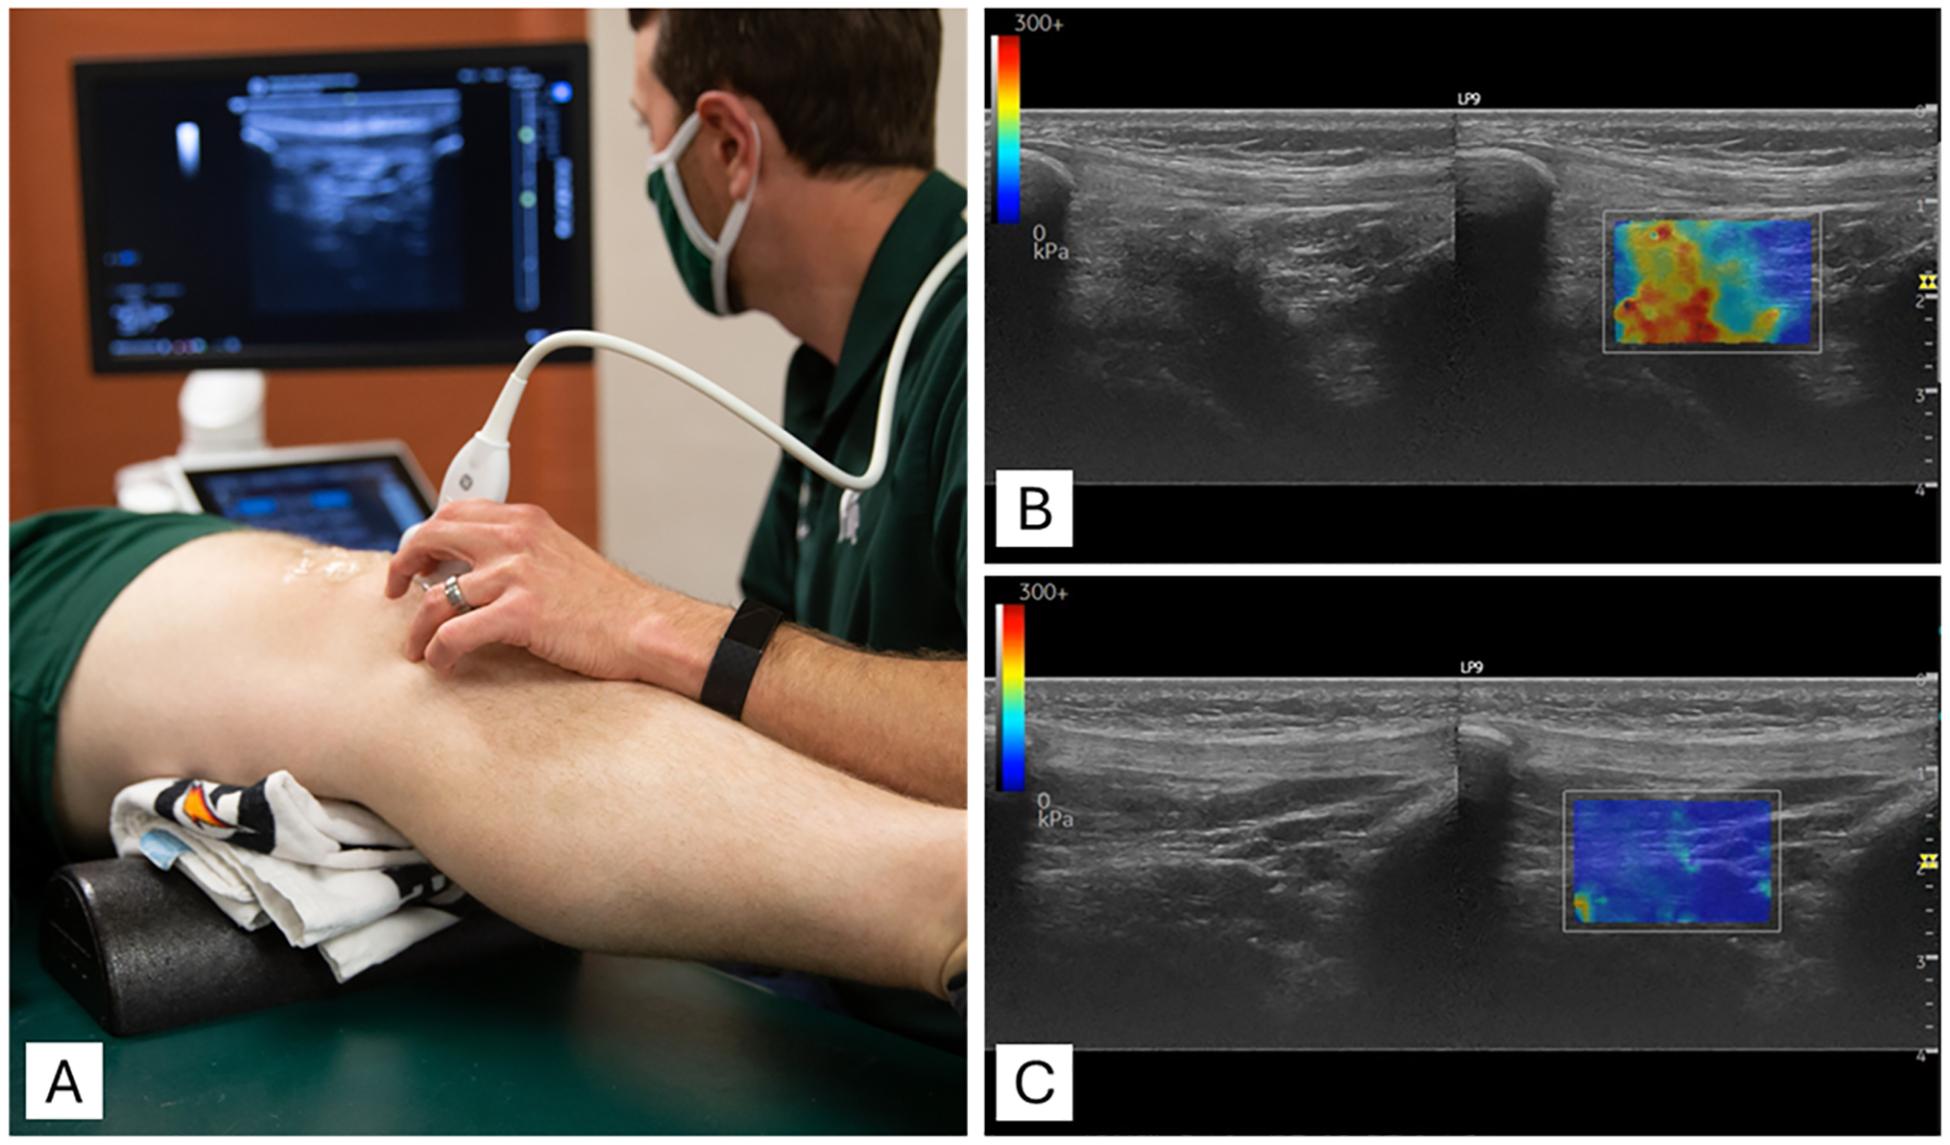

The infrapatellar fat pad (IPFP) plays an important role in knee biomechanics and inflammation, particularly following anterior cruciate ligament reconstruction (ACLR). This study investigated whether IPFP stiffness, measured with shear wave elastography, is associated with early symptoms of osteoarthritis (OA) in individuals within one year after ACLR.

DESIGN

In this cross-sectional study, 24 participants underwent bilateral IPFP stiffness assessments using shear wave elastography. Participants were positioned supine with 20° knee flexion. The stiffness limb symmetry index (LSI) was calculated to normalize stiffness between the ACLR and contralateral limbs. Early OA symptoms were defined as scores ≤85 % on at least two of four subscales of the Knee Injury and Osteoarthritis Outcome Score (KOOS). Independent -tests were used to evaluate group differences in IPFP stiffness LSI, and receiver operating characteristic curve analysis determined the optimal LSI threshold for discriminating between groups.

髌下脂肪垫(IPFP)在膝关节生物力学和炎症中起重要作用,尤其是在前交叉韧带重建(ACLR)后。本研究调查了通过剪切波弹性成像测量的IPFP硬度是否与ACLR后一年内个体的骨关节炎(OA)早期症状相关。

设计

在这项横断面研究中,24名参与者使用剪切波弹性成像进行了双侧IPFP硬度评估。参与者仰卧位,膝关节屈曲20°。计算硬度肢体对称指数(LSI)以标准化ACLR肢体和对侧肢体之间的硬度。早期OA症状定义为在膝关节损伤和骨关节炎结局评分(KOOS)的四个子量表中至少两个量表上得分≤85%。采用独立样本t检验评估IPFP硬度LSI的组间差异,并通过受试者操作特征曲线分析确定区分两组的最佳LSI阈值。